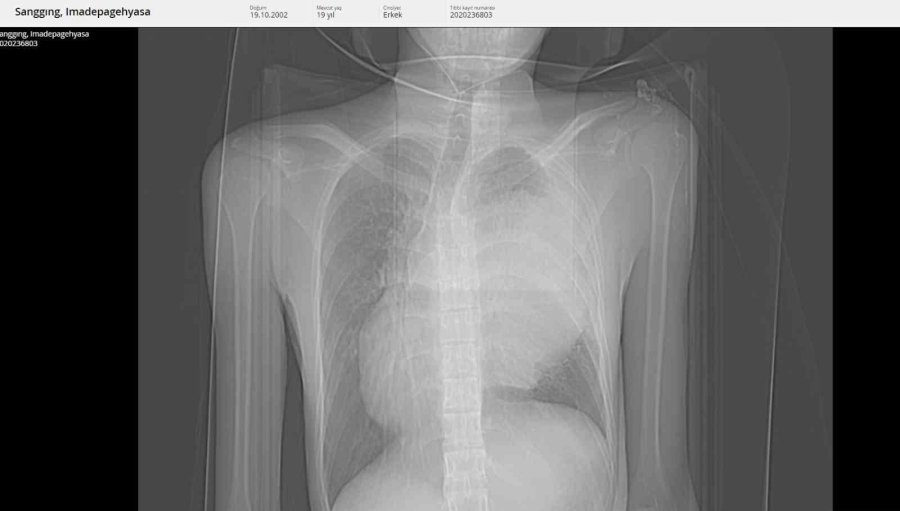

Tatil için Alanya'ya gelen 19 yaşındaki Endonozyalı I Made Pagehyasa Sanggıng, ağzından öksürükle birlikte kan gelmesi şikâyetleri ile Alanya Eğitim ve Araştırma Hastanesi Acil Servise başvurdu. Yapılan tetkik ve görüntülemeler neticesinde Sanggıng'ın sağ akciğerin tamamen fonksiyon dışı kalmasına yol açan bir kitle tespit edildi. Kitlenin ayrıca kalbe ve diğer hayati organlara da ciddi bir baskı oluşturduğu belirlendi. 19 yaşındaki hasta ALKÜ Tıp Fakültesi Göğüs Cerrahisi Anabilim Dalı Başkanı Dr. Öğretim Üyesi Oktay Aslaner tarafından acil ameliyata alındı. Başarılı geçen operasyon sonunda hasta yeniden sağlığına kavuştu. Hastanın yeniden sağlığına kavuştuğunu ifade eden Dr. Aslaner, "Acile başvuran Endonezyalı hastamızda tetkikleri sonucunda sağ göğüs kafesinin içinde dev bir kitle tespit edildi. Kalbi tamamen karşı tarafa itmiş, sol akciğerin ana atar damarını nerdeyse kapatmış şekildeydi. Ekibimle birlikte ameliyata aldık. Ameliyatta sağ göğüs kafesinden iki akciğer arasında köken alan ve sol hemotoraksı dolduran 3 kilo ağırlığında bir kitle çıkardık. Sonrasında hastanın akciğeri açıldı, kalbi rahatladı, akciğer atar damarı normal hale geldi. Kitlenin tamamen çıkarılmasıyla birlikte hasta yeniden sağlığına kavuştu. İlerleyen tıbbi cihazlar ve hastanemizdeki yoğun bakım olanakları bu tür ilerlemiş tümörlere müdahale imkânı sağlamaktadır" dedi.